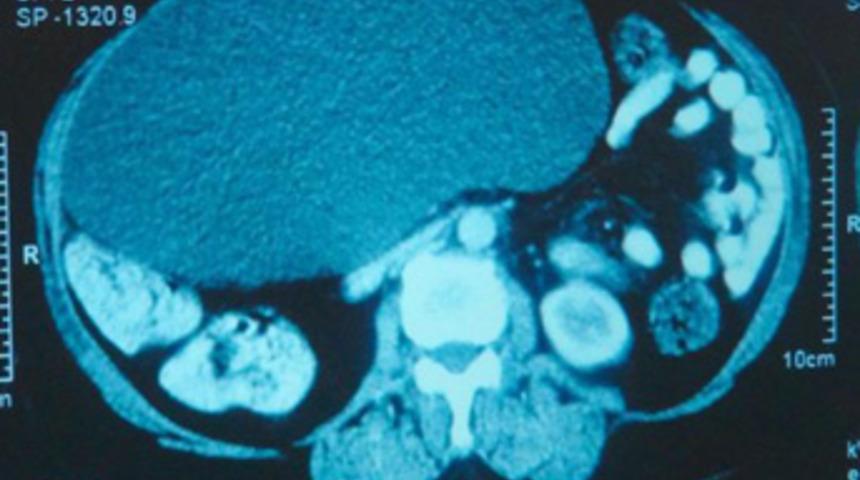

Konya'da karın şişliği ve ağrısı şikayetiyle özel bir hastaneye başvuran 5 çocuk annesi, 63 yaşındaki Emine Karadağ'ın karnından futbol topu büyüklüğünde pankreas kisti çıktı.

Emine Karadağ, son 1 ayda karnında şişlik ve ağrı olunca Özel Farabi Hastanesi'ne başvurdu. Hastanede yapılan tetkiklerde Karadağ'ın karnında pankreas kisti olduğu saptandı. Bunun üzerine Karadağ'ın karnındaki 30 metre çapında 4 kilo ağırlığındaki kist, yapılan başarılı bir ameliyatla alındı. Karnındaki şişlik ve ağrı nedeniyle birkaç hastaneye gidip doktora muayane olduğunu ve bazılarının 'Bel fıtığı olabilir' dediğini öne süren Emine Karadağ, 'Hangi doktora gittiysem, 'Bir şeyin yok' deyip gönderdiler, ama futbol topu büyüklüğünde kist çıktı. Ameliyatın ardından eski sağlığıma kavuştuğum için mutluyum' dedi.

Hastanın çok az rastlanan türden rahatsızlığı olduğunu belirten hastanenin Genel Cerrahi Uzmanı Op. Dr. Bülent Erenoğlu ise şunları söyledi:"Hastamız karın ağrısı ve şişkinliği şikayetiyle başvurdu. İlk muayenede karnını dolduran 30 santimetre çapında büyük bir kitle olduğunu tespit ettik. Hastamızın ameliyatı laparoskopi yöntemle gerçekleştirildi. Kütlenin içerisinde sıvı doluydu sıvıyı boşattıktan sonra 30 santimetre çapındaki kitleyi 1.5 santimetrelik delikten kapalı olarak çıkardık. Çok nadir görülen ve toplumda 400 kişi de 1 görülen bir hastalık. Bu boyuta ulaşanını çok az rastlanır. Yaklaşık 4 kilogram civarında bir kütleydi içerisinden de 4 litreya yakın sıvı çıkardık. Hastamızın genel durumu şu anda iyi."